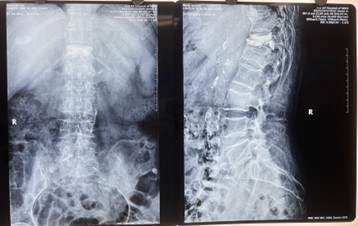

对比一些9英寸的平板C形臂,普爱医疗PLX119C大平板C形臂,30CM*30CM想(30CM*30CM)的成像范围,一次性可成像5节腰椎,有效减少小视野C形臂难以一次性确定伤椎,可能需要进行多次拍摄的问题,使得手术效率更快、更准确。